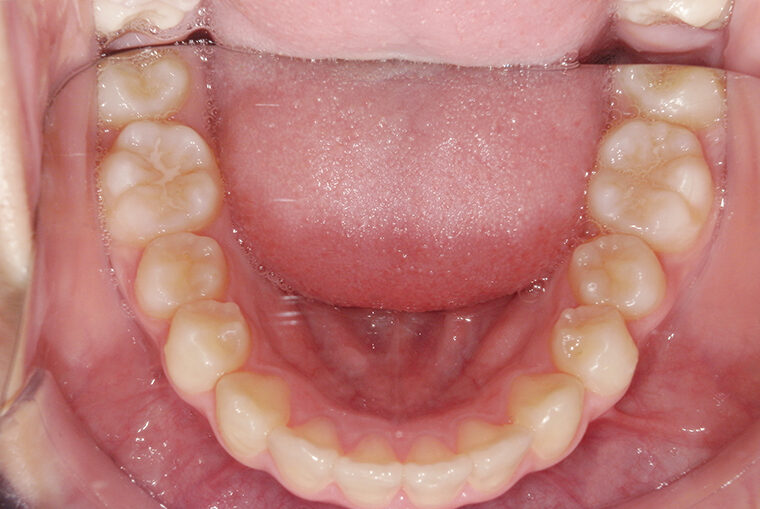

Case Study9歳女性ガタガタな歯のマウスピース矯正-矯正期間1年6ヶ月